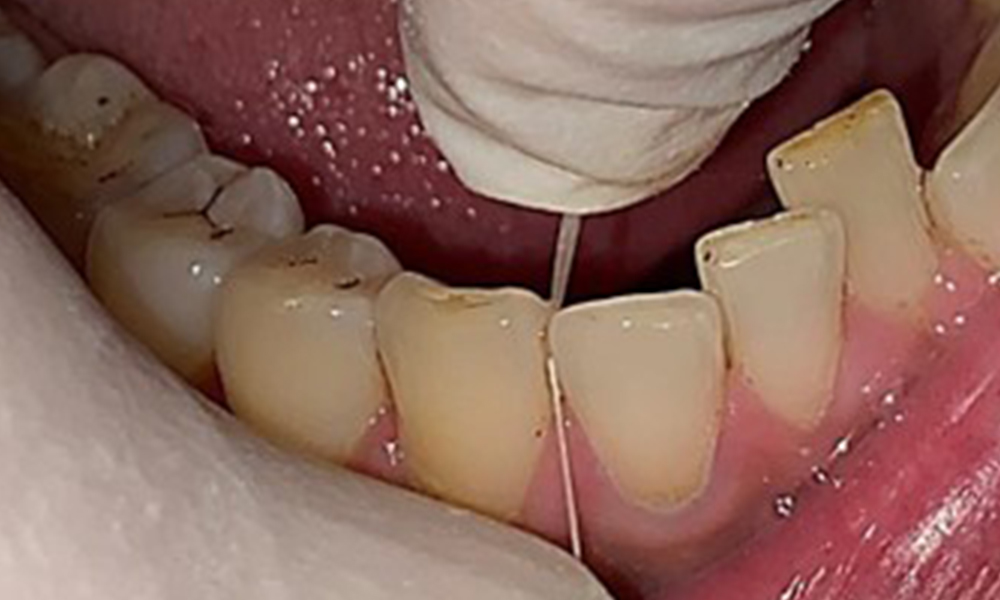

The patient has full dentition with a total of 28 teeth. There were noteworthy erosions and attritions. (Fig. 4, Fig. 5). Due to bruxism, the patient has been wearing a splint with an adjusted bite block at night for many years. The erosions were caused by long-term consumption of isotonic beverages. No periodontal bone loss or active caries were observed.

Full complement of adult teeth with no caries or radiologically recognizable bone loss was observed (Fig. 6). Radiological enamel and cusp loss were particularly evident on 36 and 37.

Instruction and motivation are important components of these appointments. Good home-based intraoral hygiene behaviour and understanding are important for patients. Plaque accumulation is particularly evident in the cervical regions (Fig. 8).